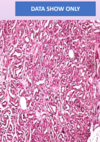

Diagnosis Describe Behavior

Hepatocellular carcinoma Section in liver which has malignant tumor formed of infiltrating trabeculae and sheets of malignant hepatocytes separated by CT. The tumor cells are polygonal Malignant